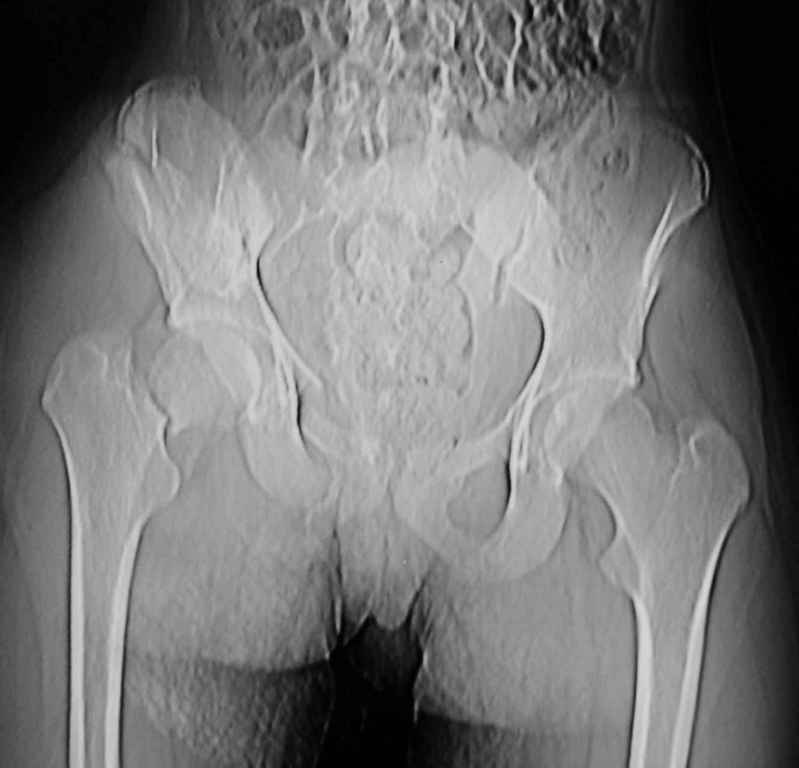

Уважаемый Алексей, на представленных Вами снимках имеется вертикально-нестабильное повреждение тазового кольца без повреждения вертлужной впадины. Учитывая это, а так же растущий возраст ребенка я бы выбрал аппарат внешней фиксации в виде кольцевой опоры, т.к. не смотря на оскольчатый перелом крыла в переднем отделе можно ввести минимум 2 стержня + 1-2 надвертлужно. Этого будет достаточно чтобы "зацепится", выполнить репозицию и дальнейшую фиксацию. Перелом шейки по моему лучше прооперировать 3 канюлированными винтами по АО.

Шейку срочно закрыто винтами.

Таз - подвздошным и падлобковым доступом раздельные рекострукционные пластины 4 штуки. Сплошную пластину как у взрослых нельзя (из-за роста придется доставать)

Perelom golovki bedra nado bylo operirovat srochno 2 boltami ( vtechenii 8 chasov posle pereloma!!!).